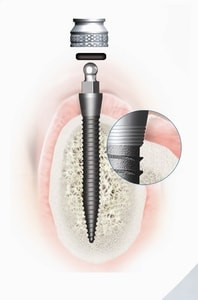

Nach Ausmessung der optimalen Implantatlänge am Röntgenbild präpariert der Zahnarzt unter örtlicher Betäubung ein minimales Loch zur Aufnahme des Implantates. In der Regel ist dafür kein Schnitt notwendig. Nach dem Eindrehen des Implantates wird das Druckknopfsystem in die Prothese eingearbeitet. Der Patient kann darauf mit einer vom Zahnarzt fixierten Prothese die Zahnarztpraxis verlassen. Er sollte in den folgenden Tagen allerdings etwas weichere Nahrung zu sich nehmen.

Mini-Implantate unterscheiden sich von klassischen Zahnimplantaten in mehreren wesentlichen Aspekten. Ein zentraler Unterschied liegt im Design der Implantate: Mini-Implantate sind einteilig, was den Eingriff vereinfacht und die Behandlungsdauer verkürzt. Klassische Implantate sind hingegen zweiteilig und bestehen aus einem Implantatkörper, einem Aufbau und dem Zahnersatz.

In Bezug auf Größe und Durchmesser sind Mini-Implantate mit einem Durchmesser von 1,8 bis 3,0 mm schmaler als klassische Implantate, die 3,5 bis 5 mm messen. Dadurch ist der Einsatz von Mini-Implantaten bei geringem Platzangebot oder eingeschränkter Knochensubstanz möglich. Für den Einsatz klassischer Implantate ist oft mehr Knochenvolumen erforderlich, was bei fehlender Knochensubstanz einen zusätzlichen Knochenaufbau notwendig macht.

3. Setzen des Mini-Implantats

Die schonende Vorgehensweise, verbunden mit einer winzigen Wunde, erspart Ihnen die sonst übliche monatelange Einheilphase. Gewebeschonende Technik, die Möglichkeit der sofortigen Belastung und vergleichsweise geringe Kosten sind neben guter Verträglichkeit und Zuverlässigkeit die Vorzüge der Miniimplantate.